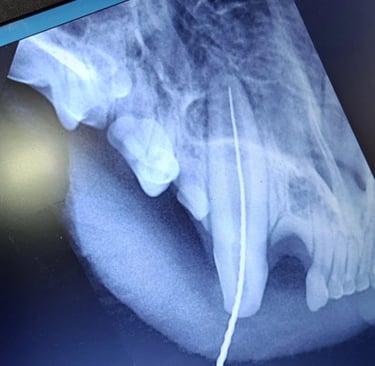

Exámenes Dentales

Revisiones completas con Radiografía Intraoral para garantizar la salud bucal de su mascota.